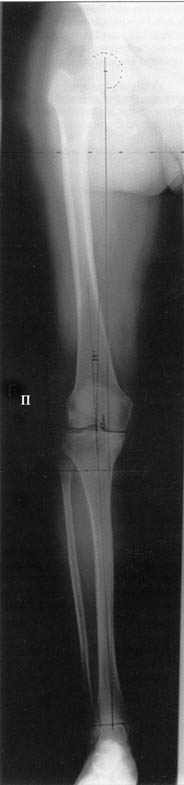

Поделитесь, пожалуйста, опытом, как Вам удается выполнять такие качественные рентгеновские снимки всей ноги полностью? На трех кассетах одновременно? Стыки кассет обычно <крадут> 1-2 см изображения. На снимке Вашего пациента <украденных> участков нет!

Качественные под нагрузочные рентгеновские снимки, получаются благодаря современному рентгеновскому оборудованию фирмы SIEMENS, (подробности могу уточнить у рентгенологов), а качественно стыковать (прозрачный скотч) научились с годами, но это для публикаций, для работы достаточно скрепить степлером по анатомическим осям с учетом толщины диафизов и грамотно расчертить. Пособие с удовольствием отправлю.